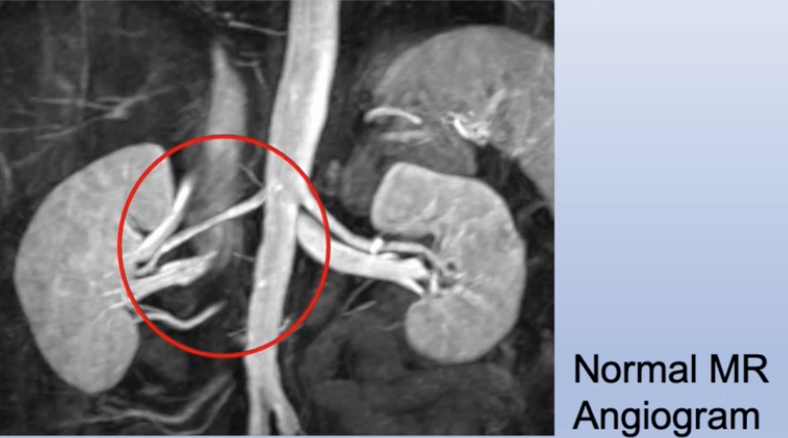

Renal Artery Stenosis

diagram shows a narrowing of Blood flow into the kidneys making the auto regulation system think blood pressure has dropped due to hypokalemia. Therefore, body will release renen and through the renen antigen system aldosterone will be released and salt and water will be retained.

Renal ultrasound, angiography & hormone estimations (cortisol/adrenaline levels) - occasionally